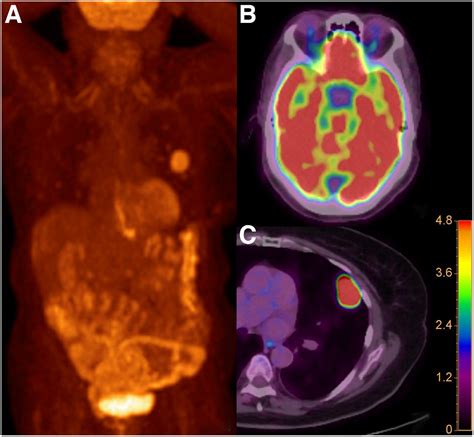

A Dotatate PET scan—often formally referred to as a Gallium-68 (Ga-68) DOTATATE PET/CT scan—is a sophisticated type of molecular imaging. Unlike conventional scans like CT or MRI, which primarily look at the size and shape of body structures, a PET scan focuses on how cells function at a molecular level.

The "Dotatate" component is a radioactive pharmaceutical agent. It acts as a targeted seeking device that binds to somatostatin receptors. These receptors are often found in high concentrations on the surface of neuroendocrine tumor cells. Because these tumors "light up" when the tracer binds to them, the PET scan creates a vivid map of where these tumors are located throughout the body, even those that are too small to be detected by standard imaging.

Once the scan is complete, the images are sent to a radiologist or nuclear medicine physician who specializes in interpreting these complex studies. They will analyze the images to identify areas of high tracer uptake, which indicate the presence of neuroendocrine tumor cells. The results are typically combined with findings from other tests and your clinical history to provide a comprehensive summary of your condition.